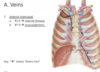

Identify the veins indicated by black & where they drain to

- posterior intervostal

- –> brachiocephalic

- 2 - 4 superior intercostal –>brachiocephalic

- 5 - 7 –> azygos system

Identify the veins indicated by black & where they drain to

- Will have 2 anterior intercostal veins

- 1 - 6 drain –> internal thoracic

- 7 - 9 drain –> musculophrenic